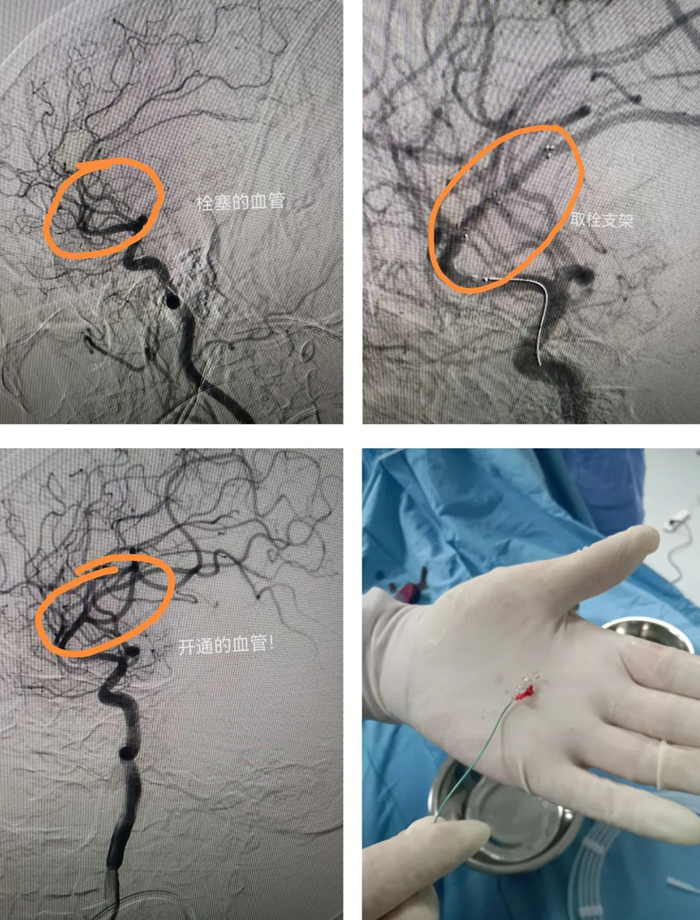

家屬簽字同意后,立刻將患者轉(zhuǎn)運(yùn)到介入室。造影提示患者為右側(cè)大腦中上干閉塞,大腦中動(dòng)脈m2段閉塞,取栓困難,風(fēng)險(xiǎn)很大。馬主任知難而上,快速上微導(dǎo)管和取栓支架,一次取栓成功,患者大腦中動(dòng)脈上干恢復(fù)血流。術(shù)后,患者肢體活動(dòng)完全恢復(fù)正常。整個(gè)過(guò)程僅用50分鐘!

腦梗死致死率、致殘率高,目前最好的治療是溶栓,但該患者正服用抗凝藥物,是溶栓禁忌癥。因此,動(dòng)脈取栓治療是該患者的最佳治療方法,可最大限度減少后遺癥的發(fā)生。(宋正峰)